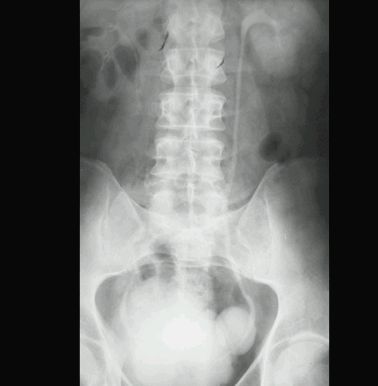

UCHYŁEK PĘCHERZA MOCZOWEGO

RTG